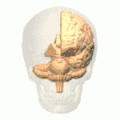

Position of marginal sulcus (shown in red). -